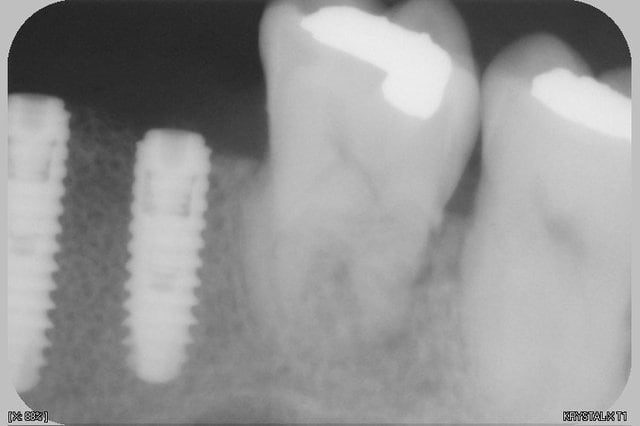

à 8 jours et pano et rétro pour compenser la déformation du pano

--